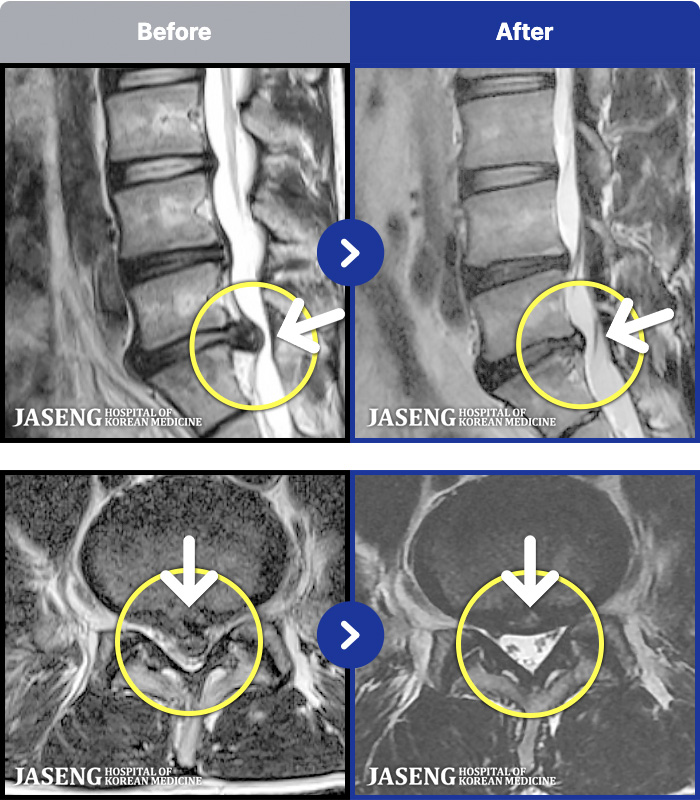

MRI ġ

1,301 MRI ũ ʸ Ȯϼ.